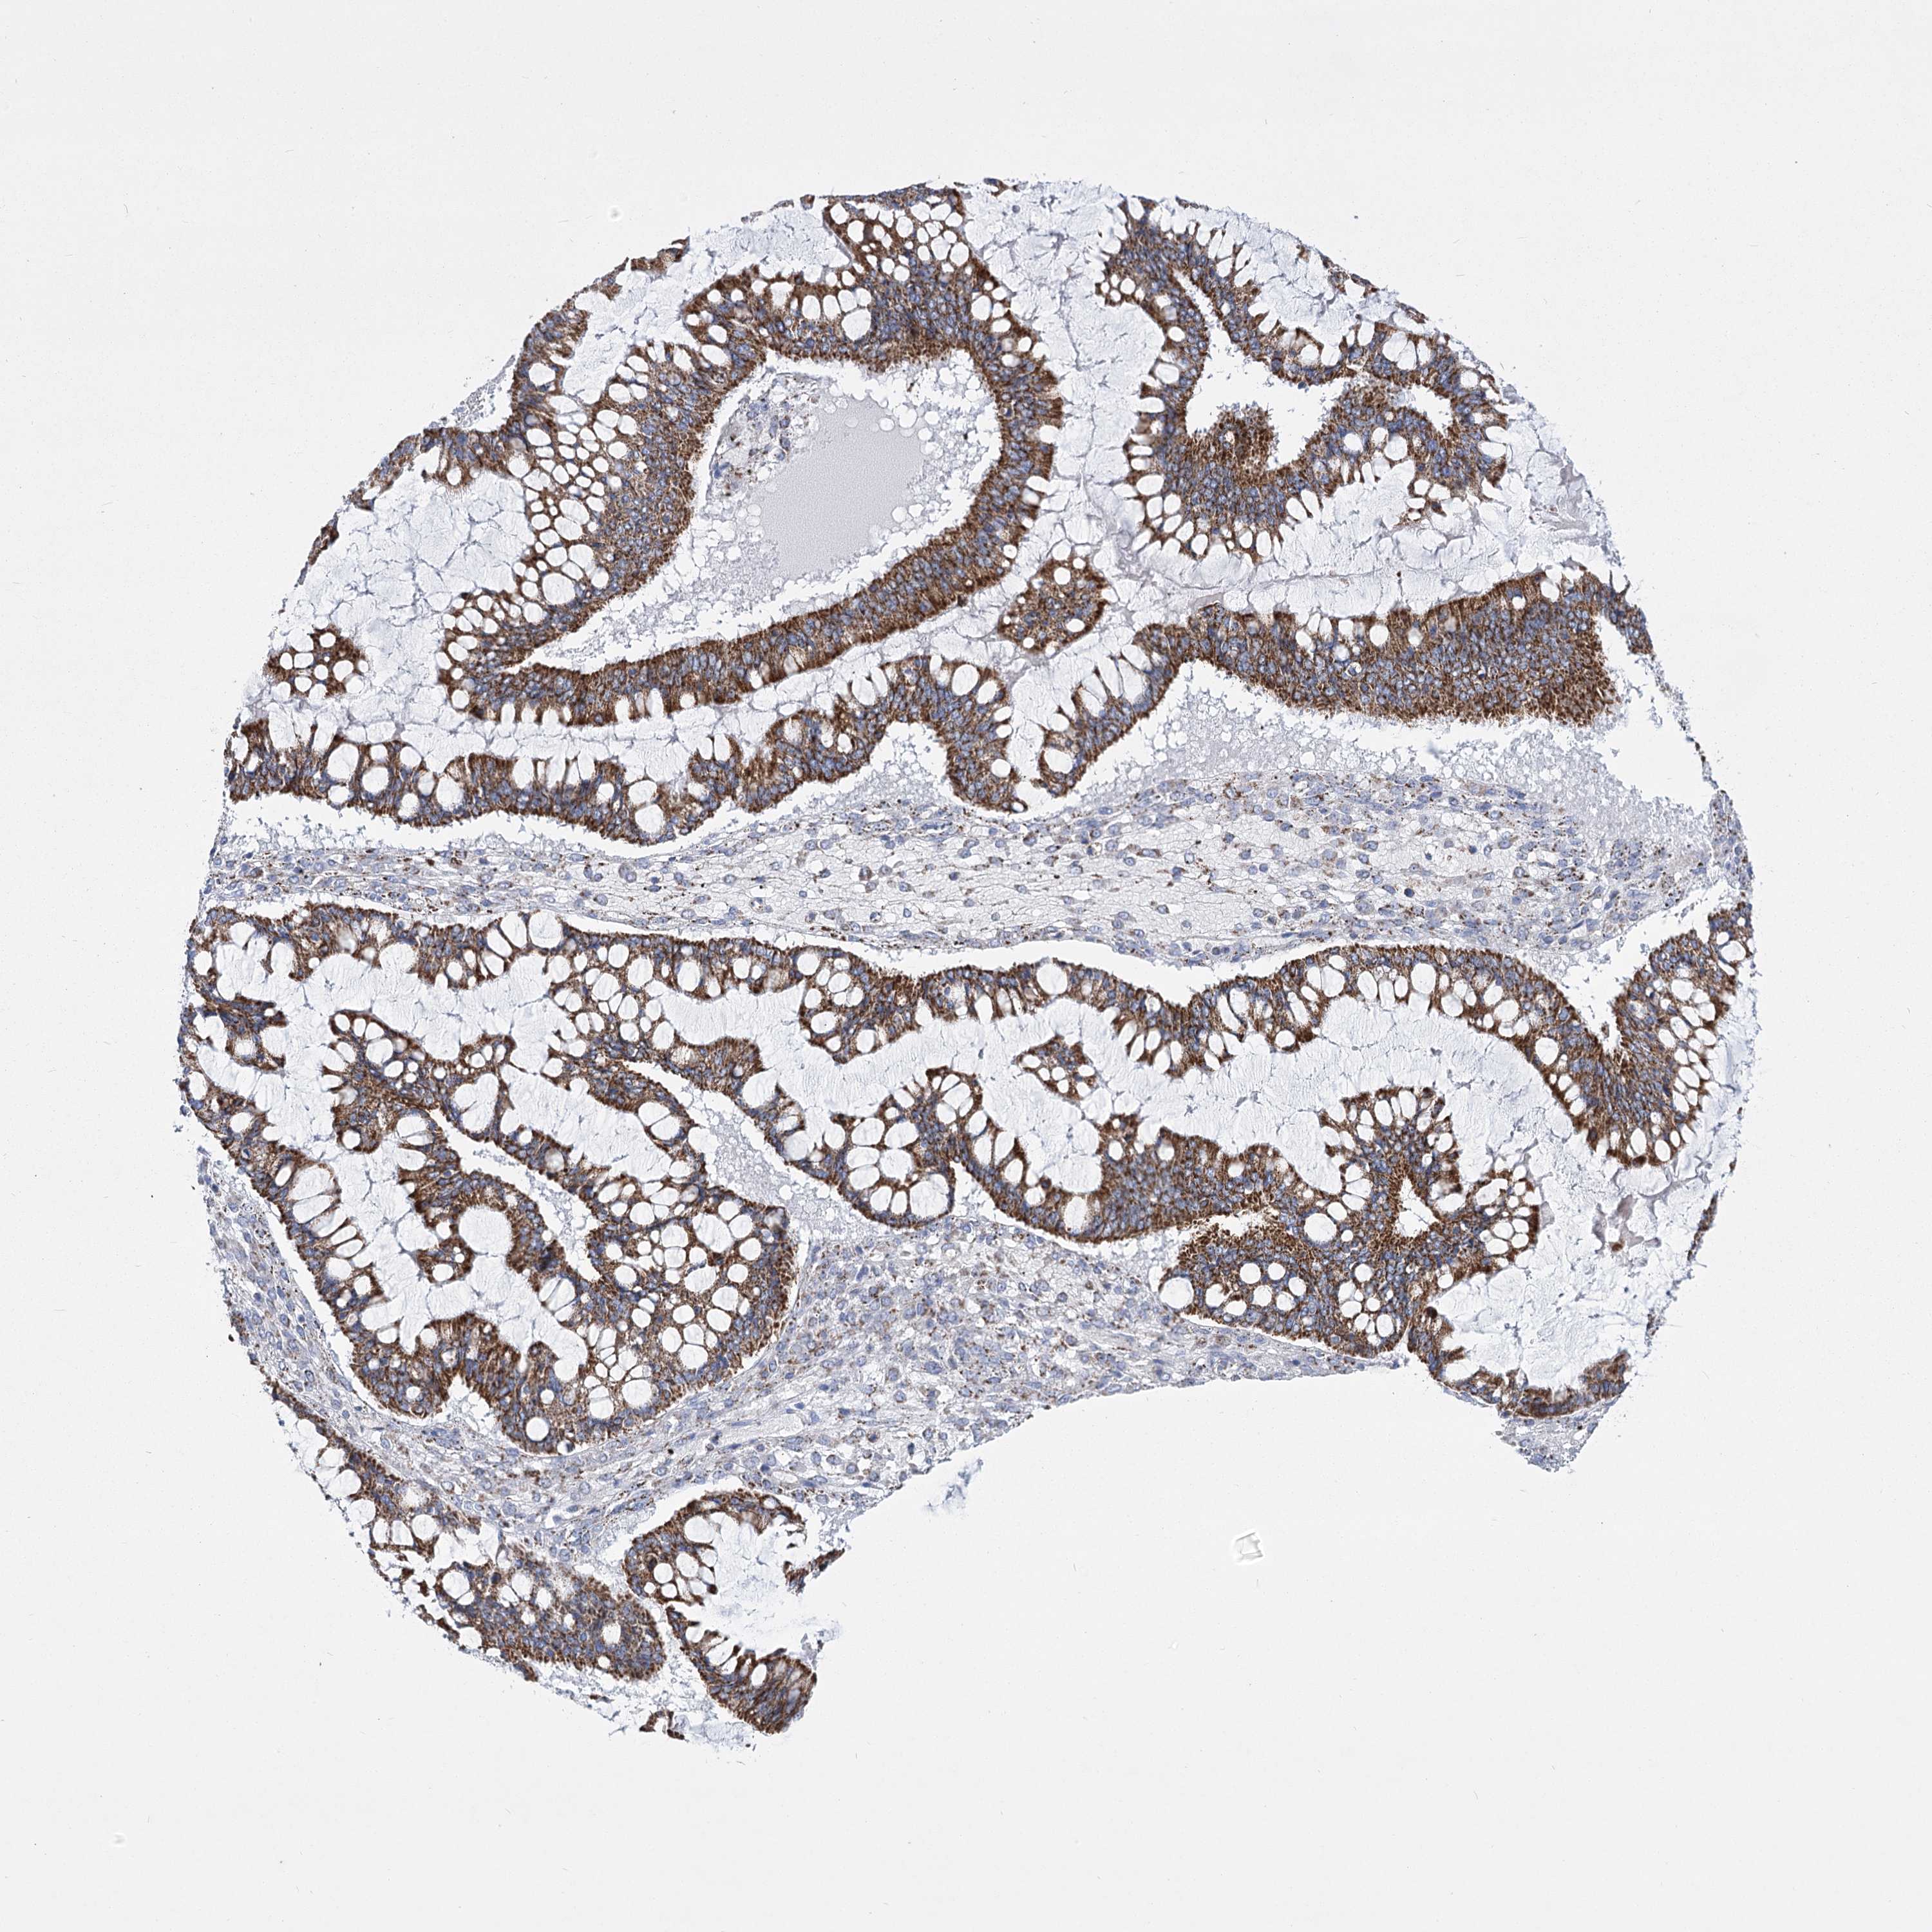

OVARIAN CANCER - Protein expressioni

A mouse-over function shows sample information and annotation data. Click on an image to view it in a full screen mode. Samples can be filtered based on level of antibody staining by selecting one or several of the following categories: high, medium, low and not detected. The assay and annotation is described here.

Note that samples used for immunohistochemistry by the Human Protein Atlas do not correspond to samples in the TCGA dataset.

Antibody stainingi

Antibody staining in the annotated cell types in the current human tissue is reported as not detected, low, medium, or high, based on conventional immunohistochemistry profiling in selected tissues. This score is based on the combination of the staining intensity and fraction of stained cells.

Each image is clickable and will lead to virtual microscopy that enables deeper exploration of all samples and also displays staining intensity scores, fraction scores and subcellular localization as well as patient and tissue information for each sample.

Antibody HPA036744

Antibody HPA036745

Antibody CAB033794

Cystadenocarcinoma, serous, NOS